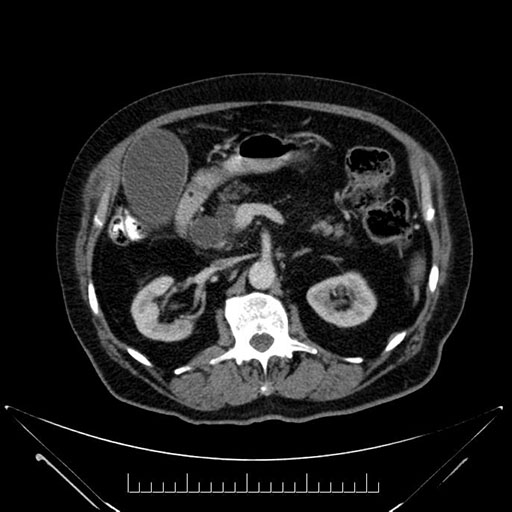

Imaging Analysis

Look through the patient's CT scan to identify any areas of concern for the necessary procedure.

Based on your CT findings, which issue(s) would give reason for "planned slowing down moment(s)" in this case?

Considering a standard Whipple procedure, what step(s) of the operation would you do differently in this case?